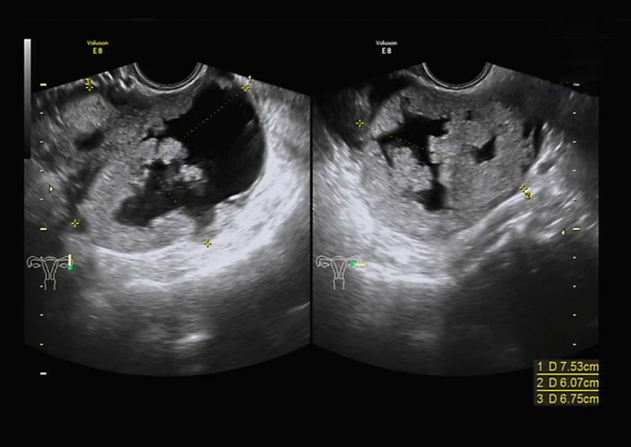

1.影像学检查 ①超声检查:可根据肿块的囊性或实性、囊内有无乳头等判断肿块性质,诊断符合率>90%。彩色多普勒超声扫描可测定肿块血流变化,有助于诊断。②磁共振、CT、PET检查:磁共振可较好判断肿块性质及其与周围器官的关系,有利于病灶定位及病灶与相邻结构关系的确定;CT可判断周围侵犯、淋巴结转移及远处转移情况;PET或PET-CT一般不推荐为初次诊断。

卵巢肿瘤超声检查

子宫水平位,如孕50天大小,内膜厚0.3cm,宫区内见多个低回声区,右卵巢3.0×2.7×2.4cm,部分囊性,内液清。左附件区见7.5×6.1×6.8cm囊实性包块,实性为主,边界尚清,周边可见部分卵巢组织,实性部分回声偏强,血流较丰富,能量多普勒提示实性部分血流丰富,RI=0.3。